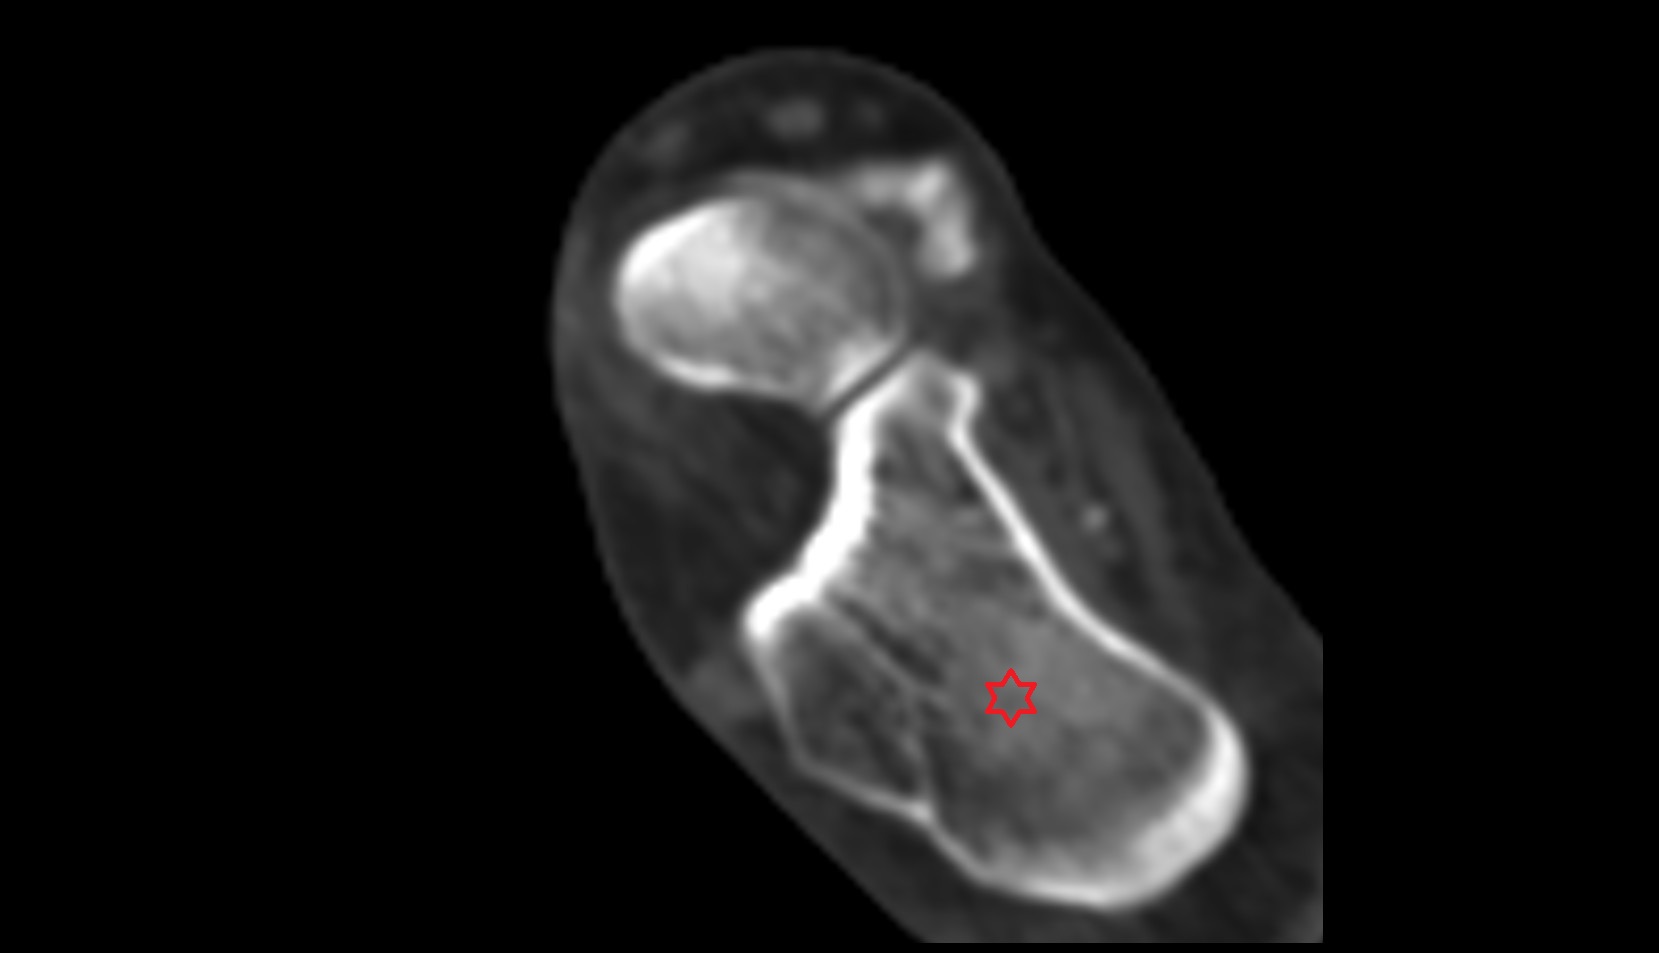

- Calcaneus